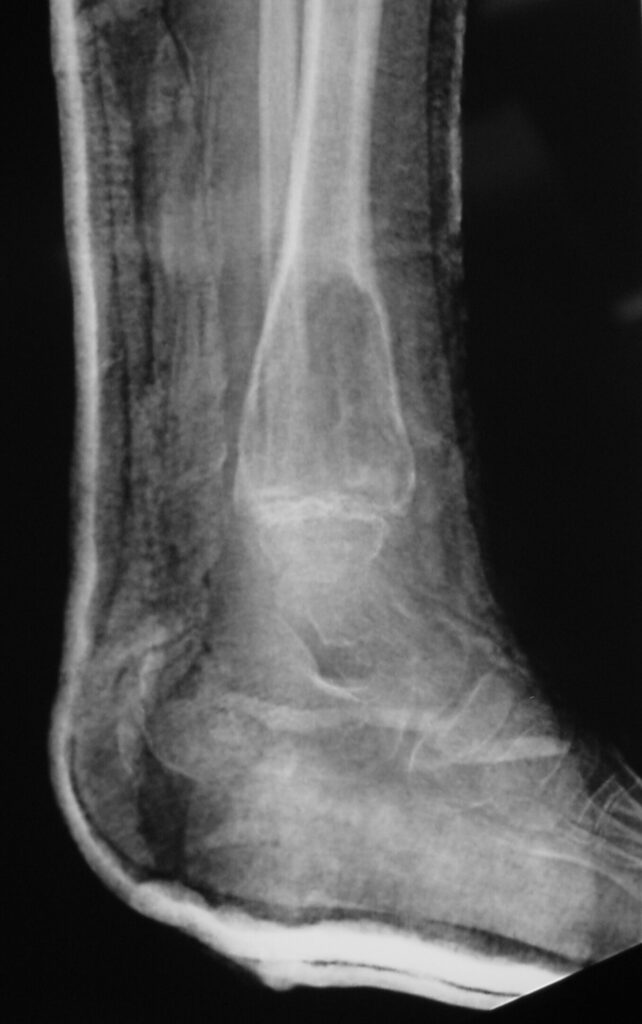

Fig 1b: Plain X-ray (Lateral View): ABC of Distal Tibia. Notice how the cortices or bony contour appears expanded. The tumor has been eroding the inner aspect of the cortex of the bone. In response the periosteum on the outside lays down new bone which gives the bone and expanded contour.

Plain x-ray

• Radiolucent

• Geographic and Eccentric lesion that is well circumscribed

• May scallop or expand the surrounding cortex

• Surrounded by sclerotic bone

• Methaphyseal region most common

• Eccentric

• Elevation of the periosteum could be seen as a benign appearing periosteal reaction (continuous periosteal reaction)